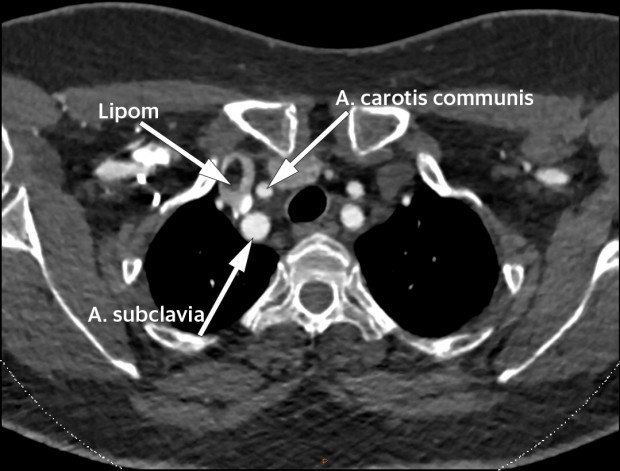

En kvinne i 60-årene med diabetes type 2 og hypertensjon ble utredet for mulig carotisstenose med CT-angiografi (kontrastforsterket CT). CT viste åpne arterier uten stenoser, men som et bifunn fant man en oppfylning i høyre vena brachiocephalica like etter konfluksen mellom vena subclavia og vena jugularis interna.

Oppfylningen målte 17 × 8 × 12 mm og hadde tetthet forenlig med fett (begge bilder). Det ble i tillegg gjort ultralyd og konkludert med at hun hadde et intravenøst lipom. Få tilfeller er beskrevet i litteraturen, de fleste lokalisert til vena cava inferior eller hjertet, men også beskrevet i vena brachiocephalica (1). Man kjenner ikke til i hvor stor grad intravenøse lipomer fører til venøs okklusjon, embolisering eller trombedanning (2). Enkelte anbefaler å fjerne lipomene, da kun histologisk undersøkelse kan skille mellom lipom og liposarkom (2, 3). Tross dette finner vi ikke ved søk i Pubmed at det er rapportert om intravenøse liposarkomer. Andre anbefaler kun å fjerne lipomene dersom de gir symptomer som følge av kompresjon eller smerte (4). Det synes som om mindre og asymptomatiske intravenøse lipomer kan observeres. For vår pasient er det derfor planlagt kontroll med MR om ett år.